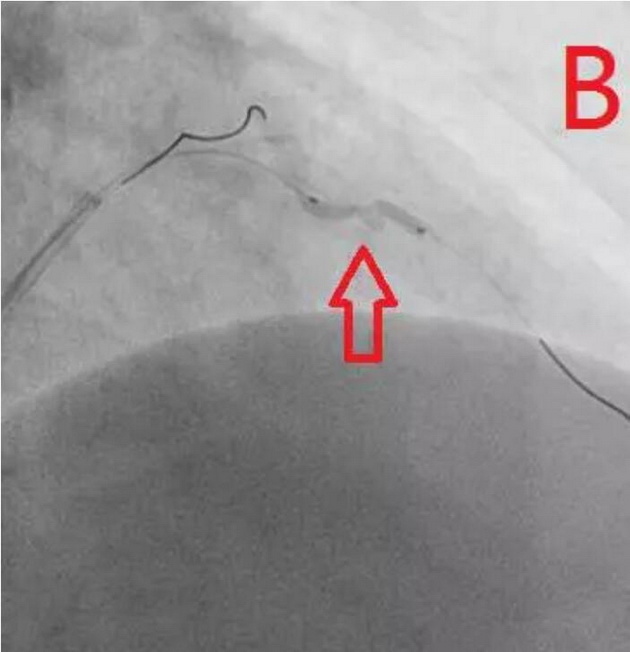

患者为77岁女性,因冠心病进行冠状动脉介入治疗,造影发现冠状动脉前降支不仅闭塞(图A),而且伴有钙化。通过不懈的努力,将闭塞的血管打开,但钙化处球囊无法将病变充分扩张(图B),意味着无法通过植入支架来维持血管管腔。于是采用血管内超声对病变处进行检测,显示病变处存在严重的360度环形钙化(图C、D)。